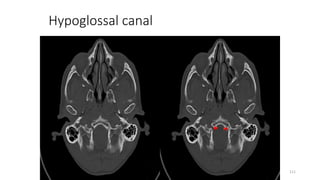

Hypoglossal canal

Content

• Hypoglossal nerve

111

Hyoglossal canal

127

HYPOGLOSSAL CANNAL